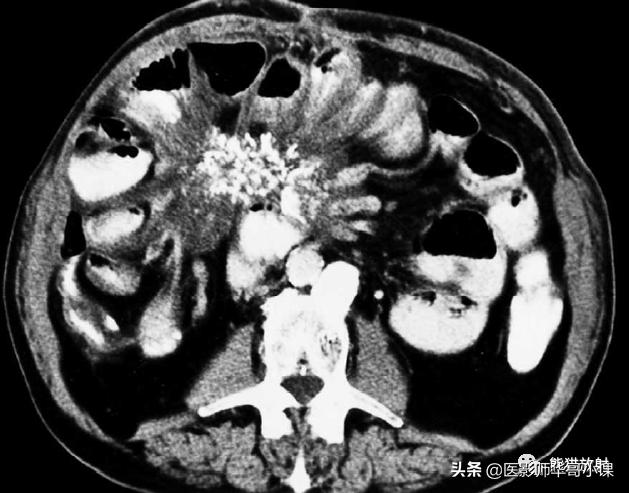

回缩性肠系膜炎CT表现 为浸润性软组织密度肿块,周围可见放射状条索影(图),这些特点可能与纤维瘤病或类癌相似。 硬化性肠系膜炎 在T1WI和T2WI图像上均呈低信号,有助于疾病的鉴别。肿块中央坏死区可见钙化(图)。该病有一定的自限性,通常预后较好。

纤维性肠系膜炎。CT表现增强CT显示大而边界模糊、广泛钙化的肠系膜软组织肿块。关注邻近的肠襻回缩及增厚。